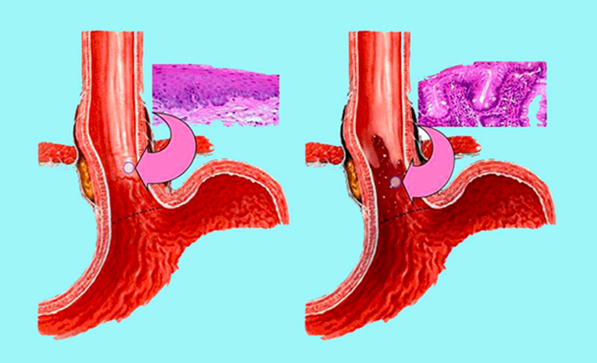

Gastroezofagealna refluksna bolest se, pored toga, povezuje i sa nastankom raka jednjaka. Oko 12 odsto obolelih od GERB ima takozvani Baretov jednjak, stanje koje se javlja kao posledica dugogodišnje hronične teške gorušice, odnosno refluksa sadržaja iz želuca u jednjak. Pod dugotrajnim dejstvom želudačne kiseline, sluzokoža jednjaka posledično menja svoju strukturu i počinje više da liči na sluzokožu želuca. Genetski je nestabilna i u stanju je da progredira u karcinom jednjaka, te je zbog toga veoma važno da se GERB, i hijatus hernija jednjaka kao njen uzročnik, na vreme prepoznaju, dijagnostikuju i leče.

Uporedna anatomija i histologija zdravog i Baretovog jednjaka

Baretov jednjak je komplikacija GERB do koje dolazi, kako je već pomenuto, zbog dugotrajnog dejstva želudačne kiseline na sluzokožu jednjaka. Zdrava, pločasto-slojevita sluzokoža koja normalno prekriva jednjak, posledično se menja u specifični metaplastični cilindrični epitel, sličan sluzokoži želuca u kome je želudačna kiselina inače prirodno prisutna. Iako će se, prema statistici, kod manje od jedan odsto osoba sa Baretovim jednjakom razviti adenokarcinom završnog dela jednjaka - malignitet sa danas najbržom stopom rasta u zapadnom svetu, koji je među karcinomima jedan od najčešćih uzročnika mortaliteta - rizik za razvoj karcinoma je 20 puta veći u odnosu na opštu populaciju.

Patološki epitel jednjaka karakterističan za Baretov jednjak može, međutim, da se ukloni bez hirurškog zahvata, endoskopskim putem - radiofrekventnom ablacijom jednjaka. Procedura se obavlja specijalnim endoskopskim instrumentima, i to sa izuzetno dobrim rezultatima o kojima svedoči više od 150 takvih intervencija izvedenih u Centru za hirurgiju jednjaka Klinike za digestivnu hirurgiju - Prva hirurška KCS, gde je procedura pionirski izvedena u ovom delu sveta. Prof. dr Simić kaže da pacijenti koji su podvrgnuti radiofrekventnoj ablaciji jednjaka mogu da budu potpuno sigurni da više nisu u rizičnoj grupi za nastanak karcinoma jednjaka, te da samo ostaje pitanje: da li će im kasnije biti potrebno da GERB leče medikamentno, ili minimalno invazivnom hirurškom procedurom.